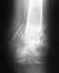

Девочка 7 лет получила неделю назад травму, на которую сначала не обратили внимания.

Поскольку она жаловалась на боли, сегодня сделали рентген, который показал компрессионный перелом 7 грудного позвонка. Завтра утром мы выезжаем в больницу райцентра. Пока ребенок лежит на животе. Ваши рекомендации по первоочередному и последующему лечению?